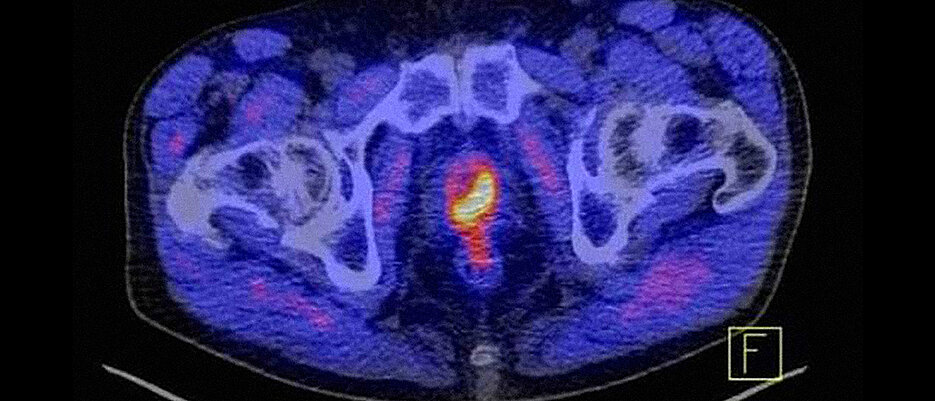

Am Informationstag haben Teilnehmende unter anderem die Chance, ihre Fragen über Prostata-Krebs (gelb-rot markiert) zu stellen.

Am Informationstag haben Teilnehmende unter anderem die Chance, ihre Fragen über Prostata-Krebs (gelb-rot markiert) zu stellen. (Bild: UKW)

Prostata-Krebs ist die häufigste Krebserkrankung bei Männern. Eine Diagnose kann Patienten und behandelnde Ärztinnen und Ärzte vor viele Fragen stellen: Welche Informationen liefern bestimmte MRT-Untersuchungen oder Fusionsbiopsien der Prostata? Was sind Vor- und Nachteile der unterschiedlichen Behandlungsansätze? Und was ist zu tun, wenn der Krebs bereits gestreut hat oder Jahre nach der Erstbehandlung zurückkehrt?